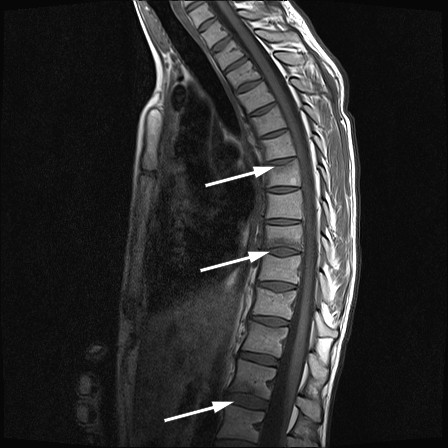

Da ryggsmertene hadde vart i tre måneder ble pasienten henvist til ortopedisk poliklinikk, der undersøkelse avdekket smerter ved palpasjon og bevegelse i torakalcolumna. MR viste frakturer og benmargsødem i øvre dekkplate i virvelcorpus T7, i nedre dekkplate i T9 (figur 1) samt i øvre og nedre dekkplate i L1 og L3 (figur 2).